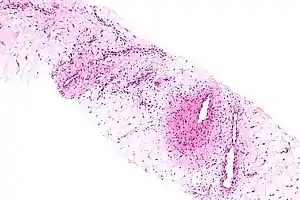

| Micrograph of an aggressive angiomyxoma. Core biopsy. H&E stain. | |

Microscopy

- Vascular appearance of tumor[7]

- Hypocellular mesenchymal lesion

- Spindled and stellate cells with an ill-defined cytoplasm

- Cells loosely scattered in a myxoid stroma

- No evidence of nuclear atypia and mitosis

- Numerous, thin-to-thick wall vessels of different sizes

- Myxoid, hypocellular background

- Bland cytological appearance of spindle cells